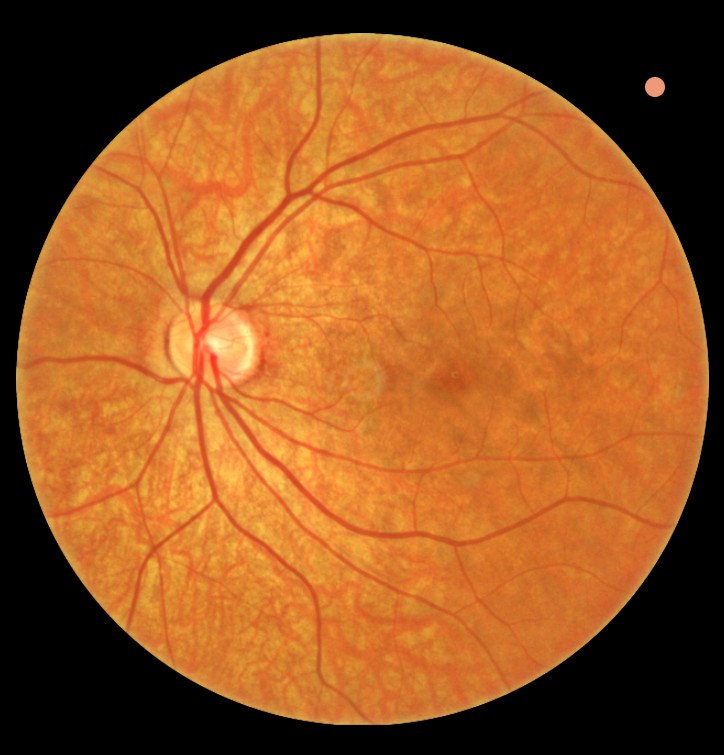

Fundusfotografie β€” digitale foto's van het netvlies die worden opgeslagen en vergeleken bij toekomstige controles om veranderingen of ziektebeelden tijdig vast te leggen

Fundusfotografie netvlies

Fundusfotografie

Regelmatig maken we digitale fundusfoto's van uw netvlies. Deze beelden worden opgeslagen en vergeleken bij toekomstige controles om eventuele veranderingen of ziektebeelden tijdig vast te leggen en te behandelen. Dit geeft een objectief beeld van het verloop over de jaren.